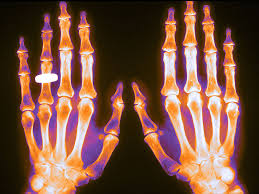

Osteoporosis inducida por glucocorticoides: conceptos novedosos e implicaciones clínicas.

Esta revisión destaca cómo el microambiente óseo responde a concentraciones suprafisiológicas de glucocorticoides y analiza las bases de la fragilidad esquelética y las fracturas. Revisa el uso y las limitaciones de las tecnologías de imagen y las herramientas de predicción actuales y emergentes, y analiza las estrategias de tratamiento osteoformador y antirresortivo, así como su uso para prevenir y tratar la osteoporosis inducida por glucocorticoides. Lancet Diabetes Endocrinol, 26 de septiembre de 2025